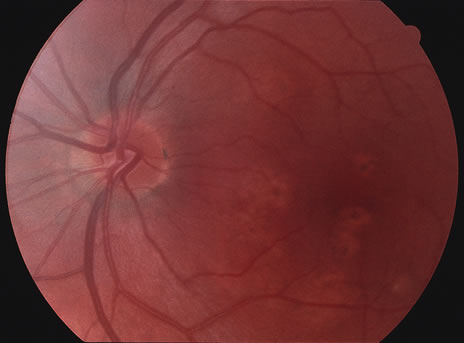

Some patients present with subretinal bands that extend between chorioretinal scars. In addition there may be initial active yellow choroidal lesions that subsequently become atrophic. Vitreous cells are usually present although they may be few and difficult to detect. Visual acuity loss in these cases may be due to active choroidal neovascularization, subretinal bands under the fovea, or from cystoid macular edema. The vast majority of affected patients are women with a mean age of 27 years and both eyes are usually involved. The affected individuals tend to be myopic.49 The age range is from 6 years to 76 years and there is no racial predilection.40 Whether it is a separate disease or a more severe form of multifocal choroiditis is controversial (Figs. 10 and 11). Aggressive therapy is warranted because it has a poorer prognosis than most cases of multifocal choroiditis. This syndrome has been called either diffuse subretinal fibrosis or progressive subretinal fibrosis syndrome.

Fig. 10. A. Fundus photograph showing the subretinal fibrosis extending from the disc to the periphery in a case of diffuse subretinal fibrosis. B. Fundus photograph showing the marked fibrosis in the midperiphery. C. Multifocal choroiditis type lesions noted in the inferior retina.

Fig. 11. A. Subretinal fibrosis in a case of multifocal choroiditis. B. Fellow eye showing classic coalescent hyperpigmented chorioretinal scars of multifocal choroiditis. These scars also can be seen in presumed histoplasmosis syndrome, but the subretinal fibrosis is extremely rare in presumed ocular histoplasmosis syndrome (POHS).